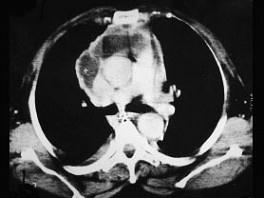

问题 男,64岁,患糖尿病,最近三天出现发热,伴颈静脉显露,结合CT图像,选择最可能的诊断 ( )

选项 A、恶性畸胎瘤 B、纵隔脓肿 C、纵隔淋巴瘤 D、侵袭性胸腺瘤 E、坏死性纵隔炎

答案 E